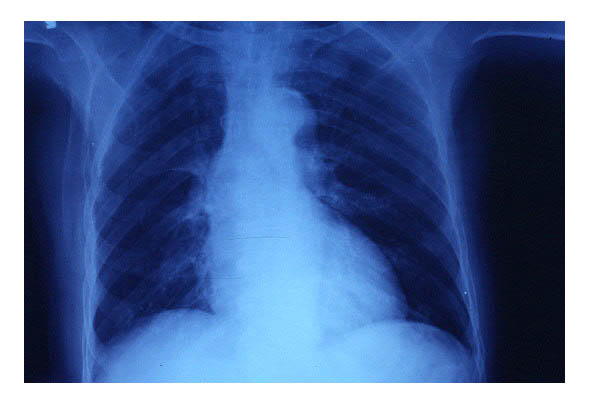

Cardiomegalia. ICC.